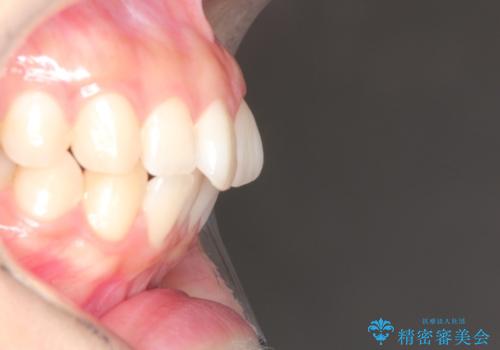

前歯のがたつきをインビザラインで目立たない矯正

- 上下の前歯のがたつきを主訴に来院されました。

マウスピースでの矯正を希望されたので、インビザラインで矯正治療を行うこととしました。

インビザラインではシュミレーションによりどのように歯が動くかを確認して矯正することができるので、患者様も安心して矯正をすることができました。